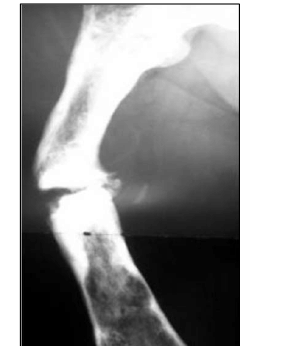

“Paciente em décimo mês de recuperação pós‐fratura apresenta a seguinte imagem radiográfica. Nega traumatismos recentes.”

É correto afirmar que trata‐se de

• A. osteomielite fistulizante.

• B. pseudoartrose hipertrófica.

• C. pseudoartrose atrófica do tipo avascular.

• D. uma fratura patológica sobre a antiga fratura.